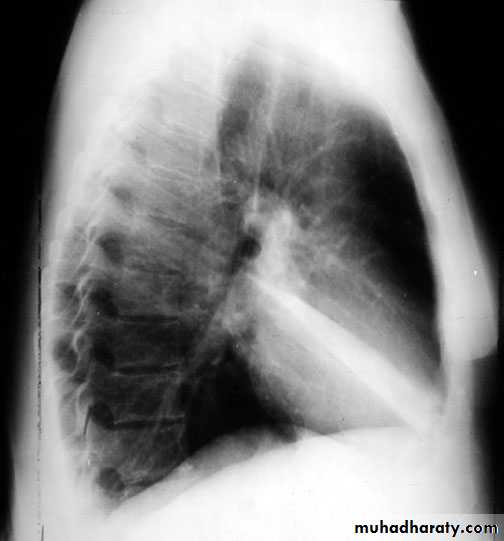

2- lateral.

Lateral view position